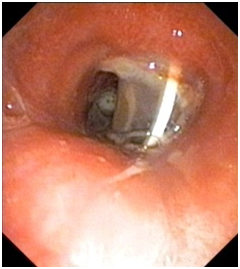

The patient was thoroughly evaluated with computed tomography scan of chest (Figure 1) and video bronchoscopy (Figure 2) and found to have severe tracheal stenosis and therefore, was planned for Tracheal Resection with end-to-end anastomosis under cross-field general anesthesia. The patient was placed supine with extended neck. The procedure was started with a transverse neck incision involving tracheostomy wound. The tracheostomy tube was removed and replaced with a sterile Flexometallic endotracheal (ET) tube with ventilatory circuit by one of the assistant through which general anesthesia was continued. Peristomal dissection was carried out and trachea freed from the skin. Cervical part of the trachea was mobilized. To reach the stenosed segment of trachea, upper median sternotomy was done. The diseased stricture segment was approximately 2cms in length and about 1.5cms from the stoma. The intervening area between the tracheostomy stoma and strictured segment was unhealthy with thinned out tracheal wall. Decision was taken to resect the trachea from proximal to stoma to distal to stenosis including the intervening unhealthy segment which amounted to nearly 4.5cms of tracheal length. In order to achieve adequate length for anastomosis, laryngeal drop was performed by extending the neck and raising the flaps. Trachea was mobilized completely and the diseased segment as described was resected. Airway was established by passing the flexometallic ET tube into the distal tracheal segment. However, adequate length for tension free anastomosis was still not achieved.

Figure 1 Coronal section of the chest computed tomography scan revealed narrowing of the tracheal lumen well above the carina with tracheostomy tube in situ.